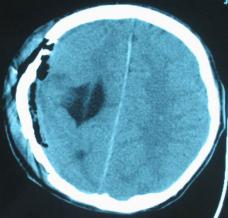

结果及随访:术后一周复查头颅CT显示脑室穿通畸形明显缩小(图6)。随访3年,未出现癫痫发作。得到很好的治疗,回归社会,正常生活学习工作。

图6:术后一周复查头颅CT显示脑室穿通畸形明显缩小